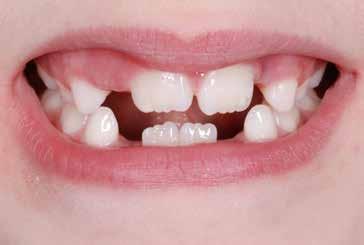

Frenuli delle Labbra

Nell’età della dentizione mista, di tutti i frenuli risulta importante soprattutto quello del labbro superiore (vedi capitolo 10). Il forte sviluppo di tale frenulo può causare la formazione di un distema mediale (Olivi et al. 2010). Per quanto concerne la diagnosi differenziale, la frenulectomia risulta indicata soltanto qualora il frenulo labiale presenti un’inserzione molto bassa e si fonda, sul lato palatale, con la papilla incisiva. Sotto il proflo radiologico, tra le radici degli incisivi superiori si osserva un’incisura che indica il passaggio interosseo delle fbre. La frenulectomia dovrebbe comunque venire effettuata solamente dopo l’eruzione degli incisivi laterali superiori Figg. 17-18

Non è sempre possibile sottoporre il paziente a queste indagini diagnostiche; per migliorare il successo e la riuscita del protocollo è necessario un approccio meticoloso ed una serie di informazioni e un’analisi dettagliata dei comportamenti per rendere il paziente collaborante, come descritto precedentemente. Questo tipo di documentazione non prevede radiografe vista la giovane età del paziente e, quindi, la diagnosi dovrà basarsi sull’esame clinico, fotografco e sull’anamnesi familiare (Snow 2005) Figg. 22-46

Il check-up ortodontico del paziente da due a sei anni Per i piccoli pazienti di questa fascia di età la diagnosi si baserà sulla documentazione fotografca, sulla documentazione video e sull’anamnesi familiare per capire se sono presenti malocclusioni in famiglia; in questa fase è molto importante analizzare tutti e due i genitori del piccolo paziente, per evitare di trovare sorprese nel corso della terapia (Baccetti et al. 2011).